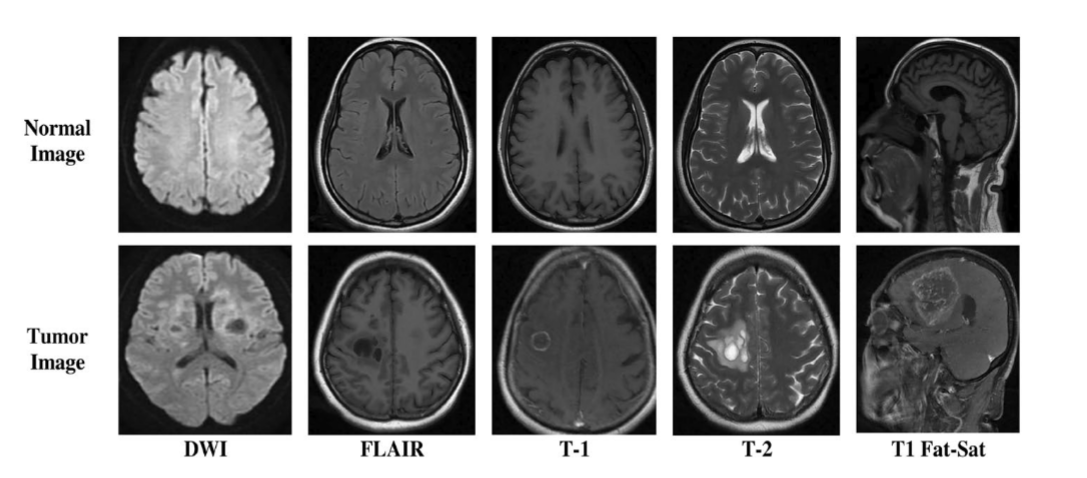

多序列MRI融合策略

多序列信息的价值

不同的MRI序列提供互补的组织信息:

| 序列 | T1加权 | T2加权 | FLAIR | DWI |

|---|---|---|---|---|

| 组织对比度 | 解剖结构 | 病变检测 | 病灶边界 | 细胞密度 |

| 脑脊液 | 低信号 | 高信号 | 低信号 | 依赖b值 |

| 白质病变 | 低对比 | 高对比 | 极高对比 | 可变 |

| 急性梗死 | 早期不明显 | 早期高信号 | 高信号 | 弥散受限 |

同一脑肿瘤的不同MRI序列对比,显示互补信息